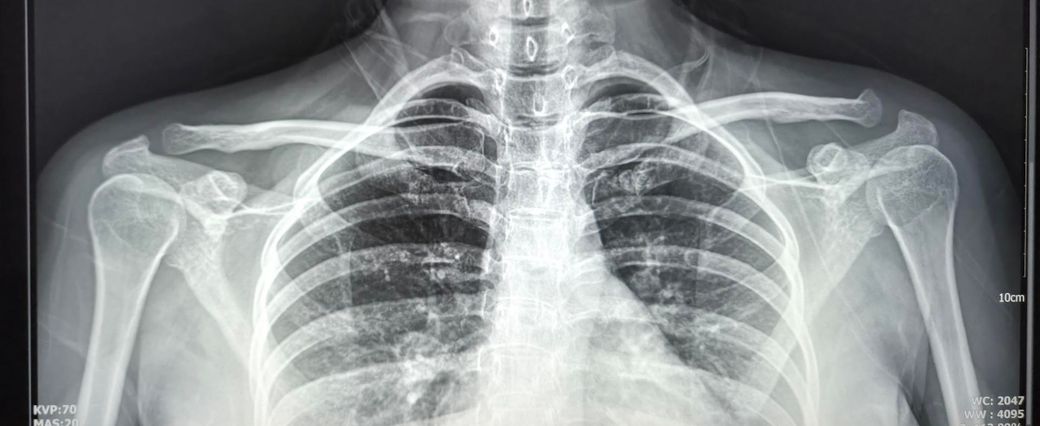

• 3번 째 사진